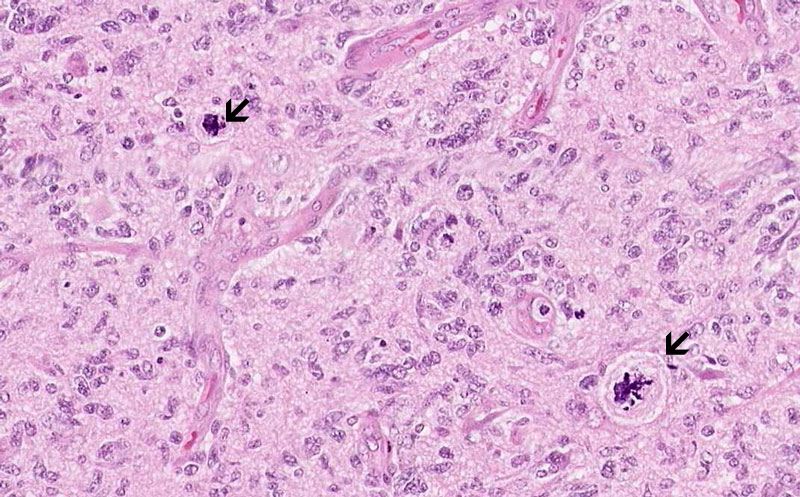

Hematoxylin & eosin

Area 2: Endothelial proliferation is also a classic feature of glioblastoma (arrow). Note that the vessels has form glomeruloid structures with complex structure and that the entothelial cells are plump and protrude into the lumen of the blood vessels.

Area 3: Mitoses, including atypical mitosess (arrow), are common in glioblsastomas.